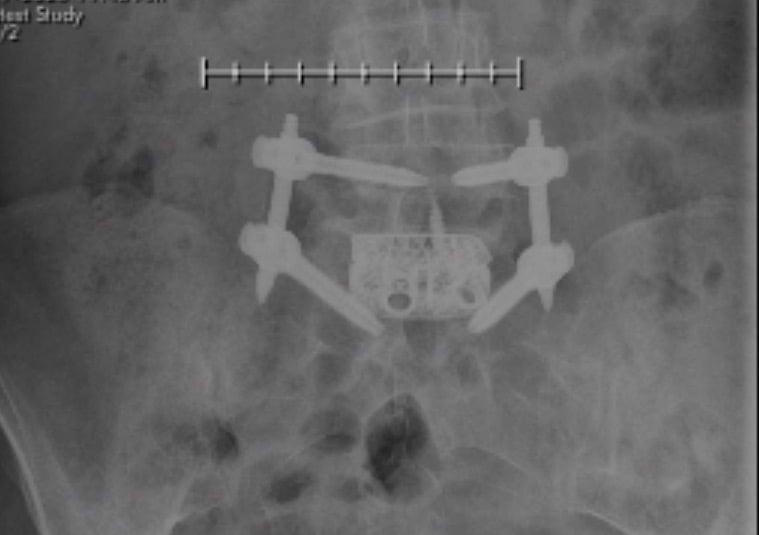

As a 23 year old guy, I never anticipated to suffer from severe back pain. I'm young, active and have a demanding job as a sports producer which sometimes involves carrying a camera for shoots. So in November of 2014, after a pick-up football game with friends, I tried to ignore the slight discomfort I felt but by March of 2015 the pain was unbearable. I shuffled my feet to walk and never slept. With the encouragement of my family, I got an appointment with Dr. James Kinderknecht. Dr. K was knowledgeable, friendly and attentive. I left that appointment with a clear plan and diagnosis - I was suffering from sciatica, a result of a herniated disc that was trapping my sciatic nerve. Dr. K recommended I meet with his colleague Dr. Andrew Sama. Dr. Sama was great! He explained that a microdiscectomy was the best route - removing the piece of the disc that was pressing on my nerve. I had surgery at HSS in April. The best part - in the recovery area post op...I was already pain free despite spine surgery! Much to my family's surprise - I was cleared to go home same day. Recovery was a process but I was up and walking the next morning. One month later I was at a friend's wedding. Two months after that - I was on vacation in Portland, OR. I was back at work in 4 weeks. As much as no one wants to hear they want surgery - it was the best decision I ever made. HSS is a great hospital and I'm grateful to Drs. Kinderknecht and Sama for their care.